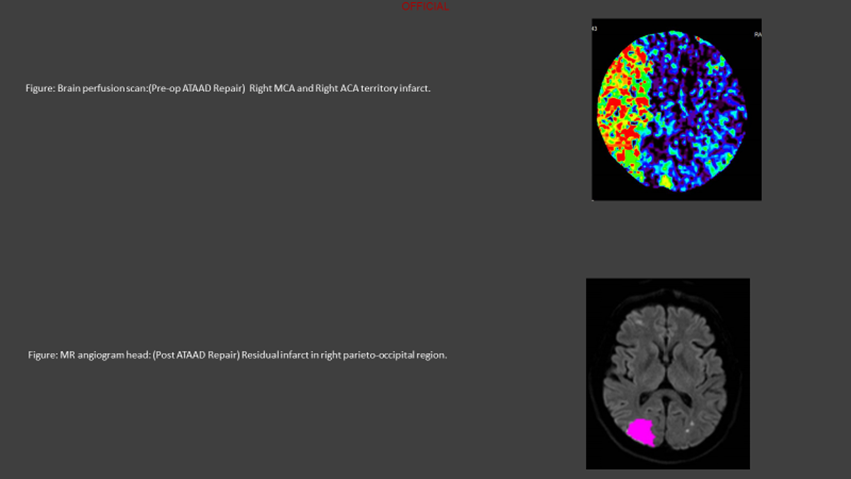

A sixty-four-year-old man presented to the emergency department with a history of syncope followed by tonic-clonic seizures and dense left hemiplegia, without chest or back pain. Because of low GCS, urgent intubation was required. Five years earlier, the patient had undergone an abdominal aortic aneurysm repair, and he had been under annual surveillance for a 45 mm ascending aortic aneurysm. On a head and neck CT with a brain perfusion scan, a significant right MCA area and right frontal lobe infarct without hemorrhagic changes were visible along with evidence of ATAAD affecting the aortic arch and its branches (Figure 2). On the gated CT aortogram, an extensive ATAAD involving arch vessels was visible from the ascending aorta to the abdominal aorta (Figure 1). Both true and false lumens supplied blood to the brachiocephalic artery, and the right common carotid artery's flow was compromised.

Figure 2

The multidisciplinary team's immediate suggestions included percutaneous fenestration and transluminal angioplasty of the right common carotid artery, followed by an MR perfusion scan to reassess cerebral circulation. Through the right common femoral artery, a successful percutaneous fenestration procedure into the right common carotid artery was carried out, and a stent was successfully deployed (Figure 3).